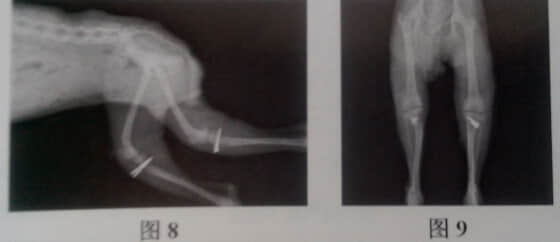

从图可见红色箭头标记的为髌骨肉側脱位,黃色箭头标记的为变形的胫骨。胸部X光片未发现异常。

手术后X光片检查髌骨以完全复位。